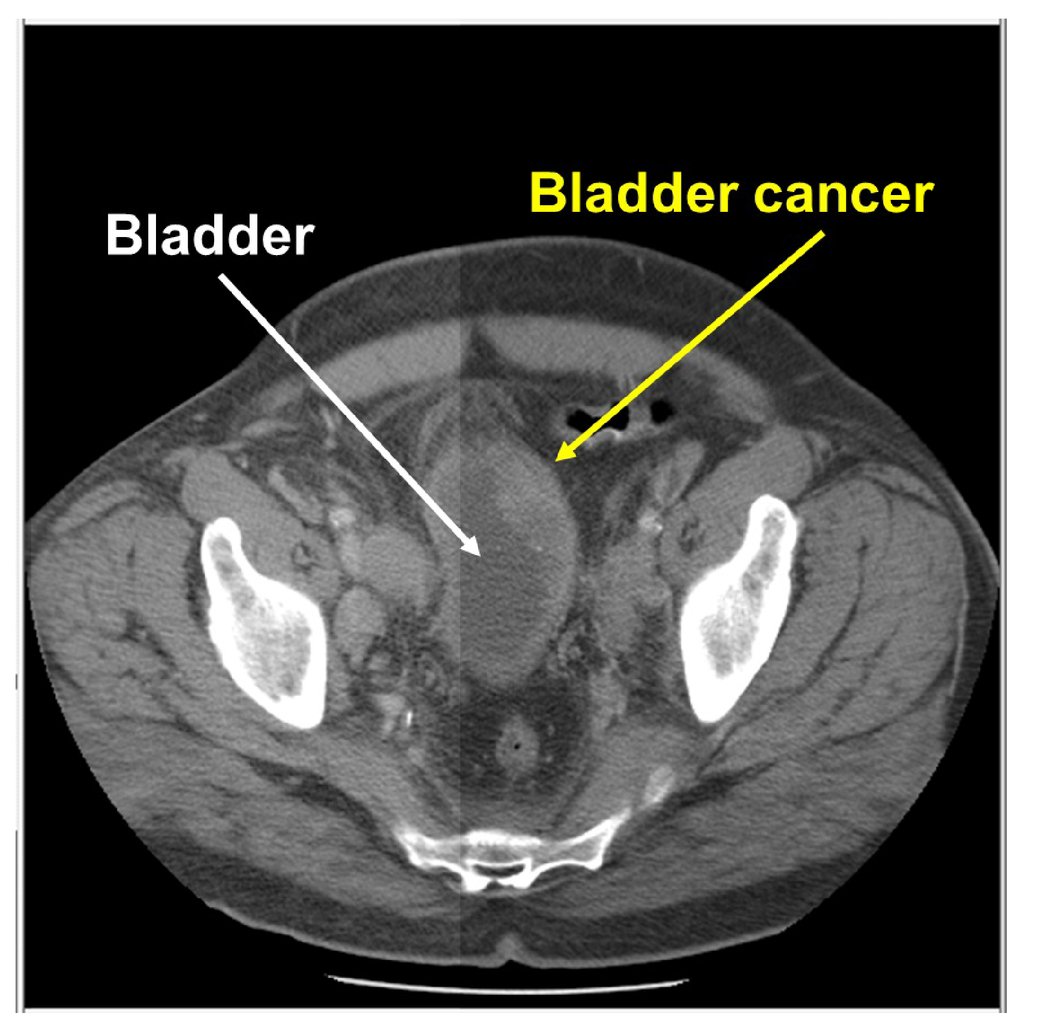

CT scan showing the location of bladder tumor. | Download Scientific …

Urothelial carcinoma of the bladder in a 59-year-old man. CT image …

do ct scan detect early bladder cancer ️ Updated Guide 2022

Bladder cancer CT – wikidoc

Bladder Cancer with CT Urography – Genitourinary Case Studies – CTisus …

CT scan of Case 1: bladder cancer mass with associated left …

CT scan showing bladder wall thickening (arrow) and decrease in tumor …

Bladder Cancer Seen Nicely on Arterial Phase Imaging but also on CT …